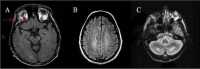

MRI findings in three persons with CTX A. Signal alterations of cerebral peduncle

Pyramidal signs (i.e., spasticity) and/or cerebellar signs are almost invariably present between ages 20 and 30 years. The clinical findings are related to the primary involvement of corticospinal tracts, subcortical white matter, dentate nuclei, and cerebellum cortex involvement that is evident on MRI [Dotti et al 1994,Inglese et al 2003,Mignarri et al 2017,Rosini et al 2017,Catarino et al 2018,Makary et al 2018].